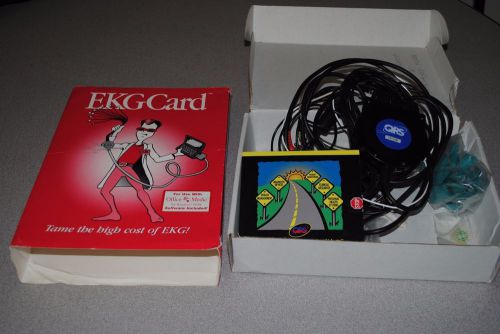

QRS Diagnostic PC-Based Universal ECG Electrode EKG